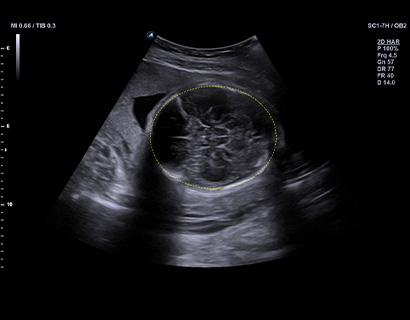

SC1-7H

X+ Crystal Signature™ convex transducer(1~7MHz)

Application:

Abdomen, EM, Gynecology, Obstetrics, Pediatric, Urology